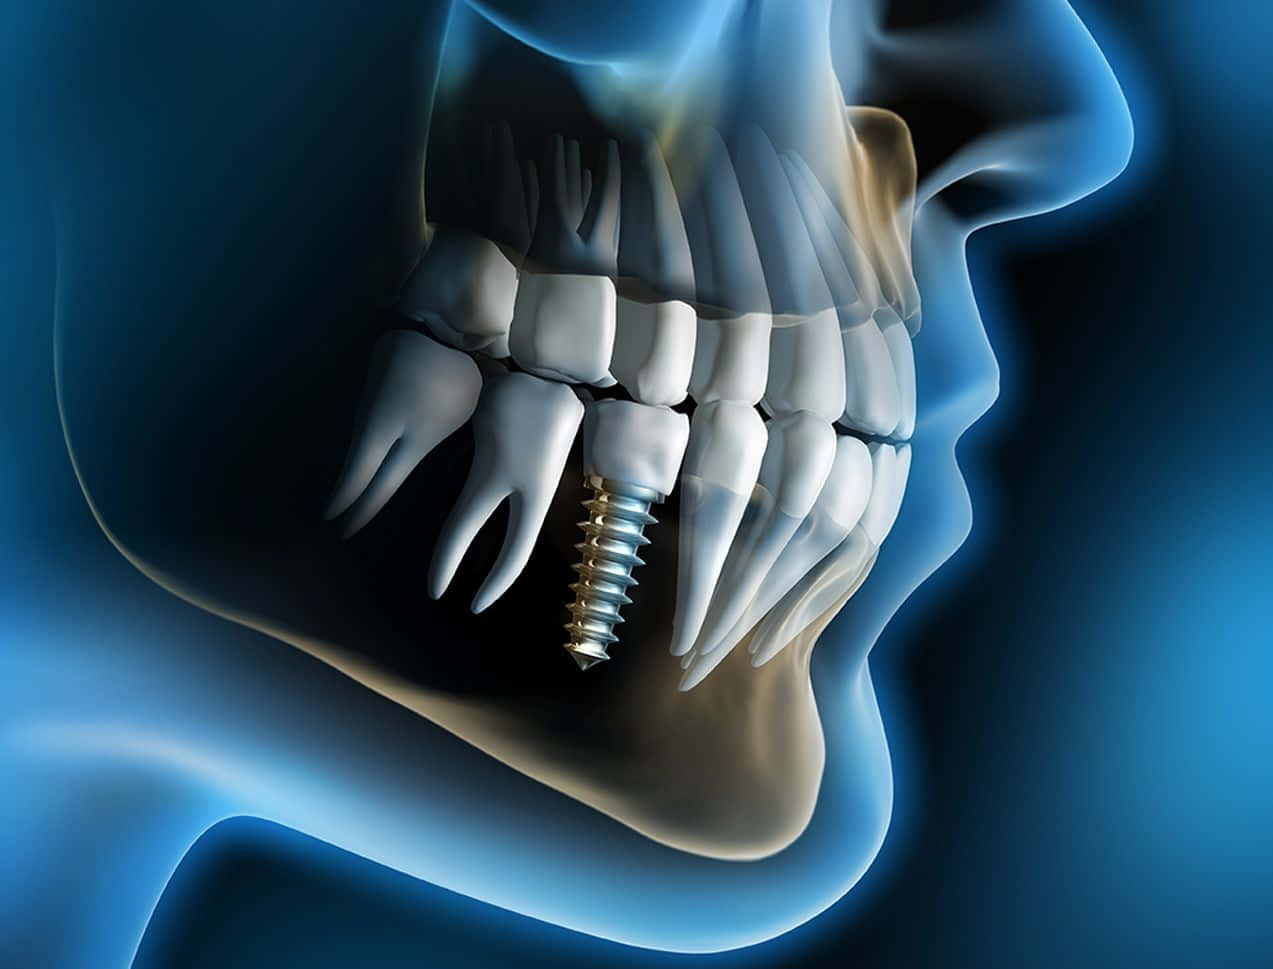

این مرکز با در اختیار داشتن کادری مجرب متشکل از دندانپزشکان عمومی، متخصصان رشتههای گوناگون و تکنسینهای حرفهای، امکان ارائه کاملترین چرخه خدمات را فراهم ساخته است. در بخش **درمانهای ترمیمی و زیبایی**، خدماتی همچون بلیچینگ (سفید کردن دندانها)، لمینیت سرامیکی و کامپوزیتی، باندینگ، و ترمیمهای همرنگ دندان با مواد باکیفیت انجام میشود. برای افرادی که با مشکل از دست دادن دندان مواجه هستند، بخش **ایمپلنتولوژی** کلینیک با استفاده از برندهای معتبر بینالمللی و تحت نظارت دقیق، جایگزینی دائمی و مطمئن را ارائه میدهد. همچنین، خدمات **ارتودنسی ثابت و متحرک** برای کودکان، نوجوانان و بزرگسالان با استفاده از براکتهای فلزی، سرامیکی و حتی روشهای نامرئی مانند اینویزیلاین، برای رفع نامرتبی دندانها و مشکلات فکی در این مرکز انجام میپذیرد.

این مرکز با در اختیار داشتن کادری مجرب متشکل از دندانپزشکان عمومی، متخصصان رشتههای گوناگون و تکنسینهای حرفهای، امکان ارائه کاملترین چرخه خدمات را فراهم ساخته است. در بخش **درمانهای ترمیمی و زیبایی**، خدماتی همچون بلیچینگ (سفید کردن دندانها)، لمینیت سرامیکی و کامپوزیتی، باندینگ، و ترمیمهای همرنگ دندان با مواد باکیفیت انجام میشود. برای افرادی که با مشکل از دست دادن دندان مواجه هستند، بخش **ایمپلنتولوژی** کلینیک با استفاده از برندهای معتبر بینالمللی و تحت نظارت دقیق، جایگزینی دائمی و مطمئن را ارائه میدهد. همچنین، خدمات **ارتودنسی ثابت و متحرک** برای کودکان، نوجوانان و بزرگسالان با استفاده از براکتهای فلزی، سرامیکی و حتی روشهای نامرئی مانند اینویزیلاین، برای رفع نامرتبی دندانها و مشکلات فکی در این مرکز انجام میپذیرد.

درمانگاه جاماسب حکیم با درک اهمیت درمان ریشه اصولی، بخش **اندودانتیکس (درمان ریشه)** مجهزی دارد که با کمک میکروسکوپ دندانپزشکی، درمانهای پیچیده ریشه را با دقت و موفقیت بالایی انجام میدهد. بخش **پریودانتیکس (درمان بیماریهای لثه)** نیز به تشخیص و درمان تخصصی مشکلات لثه از جمله جرمگیری عمقی، جراحیهای لثه و مدیریت التهابهای پیشرفته میپردازد. برای کودکان، **دندانپزشکی اطفال** با فضایی صمیمانه و روشهای مناسب، به مراقبت از دندانهای شیری و دائمی، فیشورسیلانت و آموزش بهداشت اختصاص یافته است. علاوه بر این، خدمات **جراحی دندانهای عقل، پروتزهای ثابت و متحرک (دندان مصنوعی)**، و **خدمات رادیولوژی دیجیتال (عکس OPG و تکدندانی)** به صورت درونکلینیکی، تشخیص و درمان را تسهیل و یکپارچه میسازند.

این مرکز صرفاً یک مجموعه عمومی نیست. حضور **متخصصان مجرب** در رشتههای اندودانتیکس (درمان ریشه)، پریودانتیکس (لثه)، ارتودنسی، پروتز و ایمپلنت، کیفیت درمان را به سطحی بالاتر میبرد. این تخصص، با **پیشرفتهترین تجهیزات** مانند میکروسکوپ دندانپزشکی، رادیولوژی دیجیتال (OPG) و سیستمهای طراحی دیجیتال لبخند ترکیب شده تا دقیقترین تشخیص و کمتهاجمیترین درمانها ممکن گردد.

این مرکز صرفاً یک مجموعه عمومی نیست. حضور **متخصصان مجرب** در رشتههای اندودانتیکس (درمان ریشه)، پریودانتیکس (لثه)، ارتودنسی، پروتز و ایمپلنت، کیفیت درمان را به سطحی بالاتر میبرد. این تخصص، با **پیشرفتهترین تجهیزات** مانند میکروسکوپ دندانپزشکی، رادیولوژی دیجیتال (OPG) و سیستمهای طراحی دیجیتال لبخند ترکیب شده تا دقیقترین تشخیص و کمتهاجمیترین درمانها ممکن گردد.